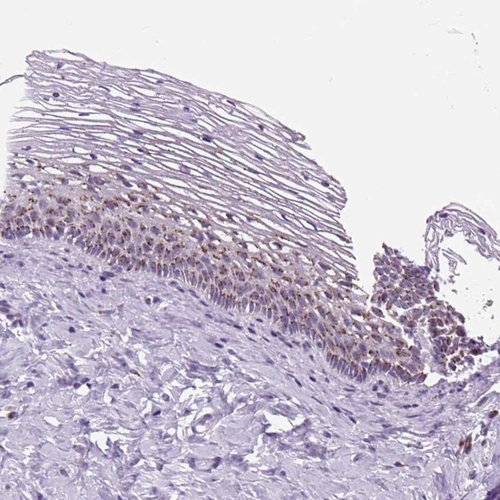

Immunohistochemistry analysis in human cervix, uterine and skeletal muscle tissues using Anti-GORASP1 antibody. Corresponding GORASP1 RNA-seq data are presented for the same tissues.